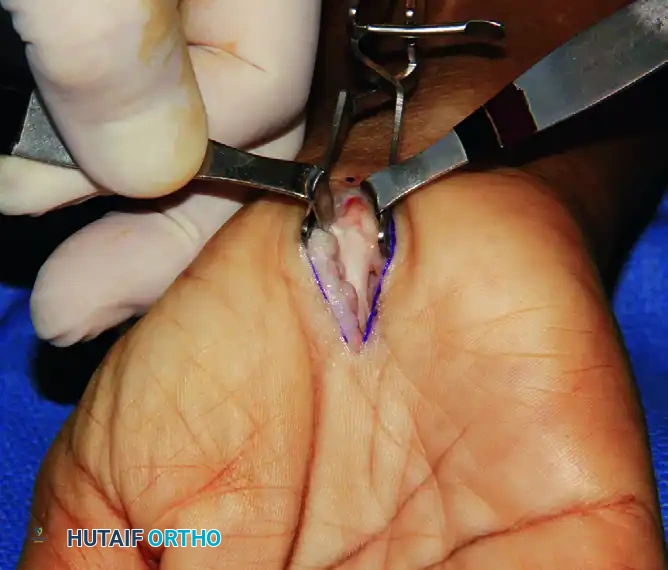

Exposure of the transverse carpal ligament (TCL) following the retraction of parallel palmar fascia fibers and hypothenar fat.

Step 3: Division of the Transverse Carpal Ligament

- Identify the proximal and distal extents of the TCL.

- Carefully divide the TCL longitudinally, staying strictly to the ulnar side of the median nerve to avoid the recurrent motor branch.

- Once the TCL is completely divided, use Metzenbaum scissors to divide the distal 2.0 cm of the antebrachial fascia proximally beneath the wrist crease.

- Verify that the distal aponeurotic fibers between the thenar and hypothenar muscles are completely released.

After the division of the TCL, the distal 2.0 cm of the antebrachial fascia is divided proximally with Metzenbaum scissors.